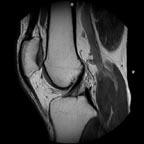

The performance of the MSK Extreme 1.5T’s gradient system reportedly exceeds that of any clinical MRI today. Its 70 m/Tm gradient strength with slew rate of 200 T/m/s achieves a new level of visualization of articular cartilage and detail resolution reportedly resulting in exceptional image quality.

“The ONI MSK Extreme 1.5T delivers images with high spatial resolution of small structures within the hand and wrist which are superior to most whole body MRI systems,” said Douglas W. Goodwin, M.D., director of musculoskeletal radiology, Dartmouth-Hitchcock Medical Center.